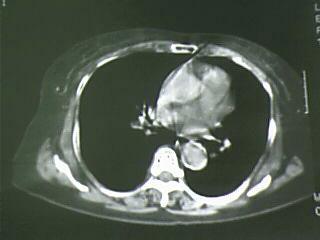

以下是引用杀毒软件在2009-4-14 17:52:00的发言:[br]考虑---右肺继发型肺结核---纵隔淋巴结多发钙化----左肺支扩

以下是引用黑白光影在2009-4-14 20:36:00的发言:[br]右肺继发型肺结核;左下慢性支气管炎性病变。